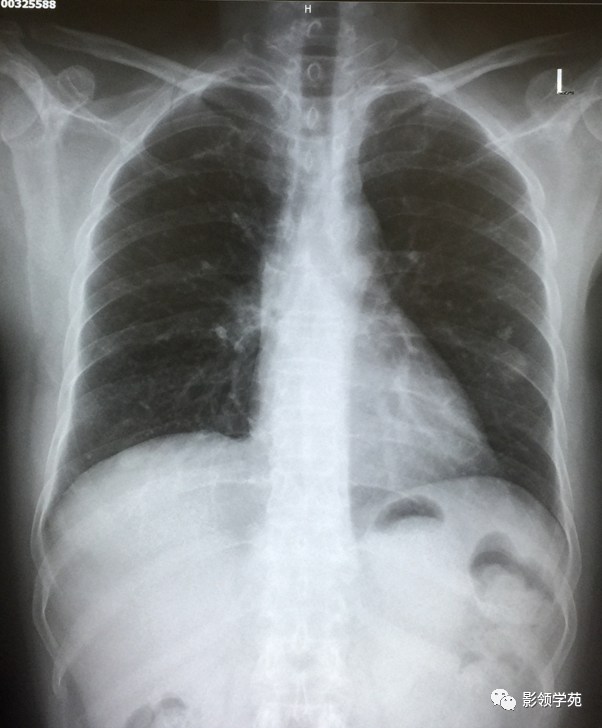

瘤外科患者,女,48岁,左乳癌根治术后2月术后化疗。病理:左乳伴髓样癌特征的乳腺浸润性导管癌。术后TAC方案化疗1个周期。

左乳切除术后,左肺下野两个大小不等高密度影。